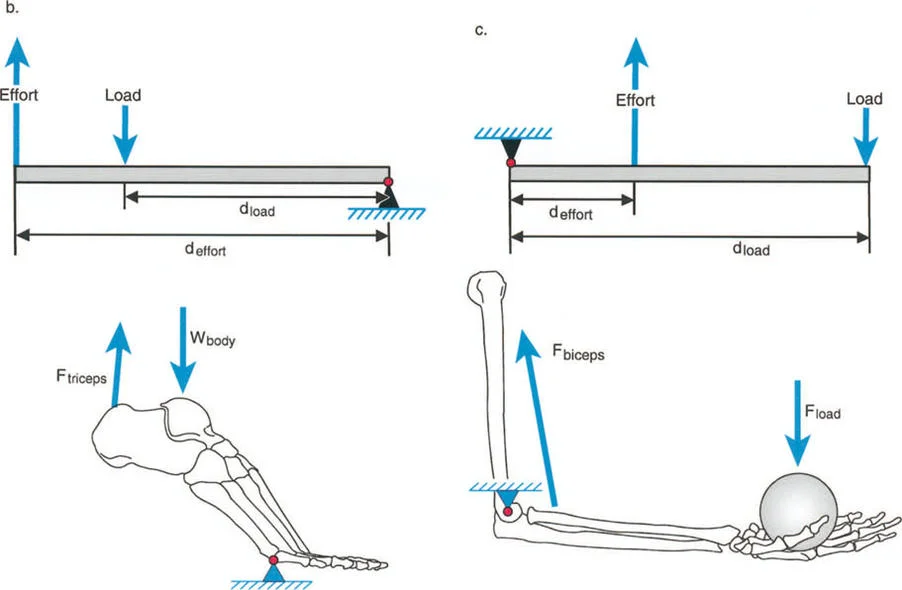

يشير خلل وظيفة الذراع الرافعة إلى التغيير المرضي في علاقات الرافعة الطبيعية بين ثلاثة مكونات حاسمة:

1. الحمل (The Load): الوزن أو المقاومة التي يجب التغلب عليها.

2. الجهد (The Effort): القوة العضلية المطبقة لتحريك الحمل.

3. موضع نقطة الارتكاز (The Fulcrum Position): المفصل الذي يحدث حوله الدوران.

بشكل خاص، يصف خلل وظيفة الذراع الرافعة حالة سريرية تتشوه فيها أذرع الرافعة الداخلية و/أو الخارجية بسبب سوء محاذاة العظام، أو التشوهات الالتوائية، أو تيبسات المفاصل الموضعية.

تاريخياً، كان جراحو العظام بطيئين في إدراك الأهمية القصوى لخلل وظيفة الذراع الرافعة، وغالبًا ما كانوا يركزون فقط على تحرير الأنسجة الرخوة أو نقل الأوتار. غالبًا ما يؤكد التدريب الجراحي على التفكير في العضلات على أنها مجرد مولدات طاقة بيولوجية. ومع ذلك، فإنه قانون أساسي في الفيزياء أن الطاقة لا يمكن توليدها أو نقلها أو استخدامها دون الاستفادة من أذرع الرافعة الهيكلية التي تتصل بها تلك العضلات.

بمجرد أن يبدأ الجراح في التفكير من حيث "العزوم" التي تولد القوة، بدلاً من مجرد انقباض عضلي معزول، فإنه يبدأ تلقائيًا في فحص النصف الآخر من المعادلة الميكانيكية: الرافعة نفسها.